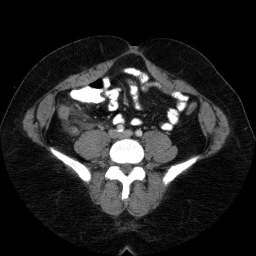

This is an image from a contrast enhanced abdominal CT.

These are images from a contrast enhanced abdominal CT.

Fluid in the right paracolic gutter, and a thickened, inflamed appendix with thickening of the adjacent cecal wall.

Differential: Acute appendicitis is by far the most likely diagnosis.

No appendicolith is seen in this case.

The appendix is normally less than 7 mm in diameter, or if fluid filled, the wall can be up to 3mm thick. This appendix is distended, and the adjacent stranding and fluid indicates the inflammatory process which is causing peritoneal irritation and pain. Here is a series of images showing a normal appendix using similar technique. Note the thin walls of the normal appendix.